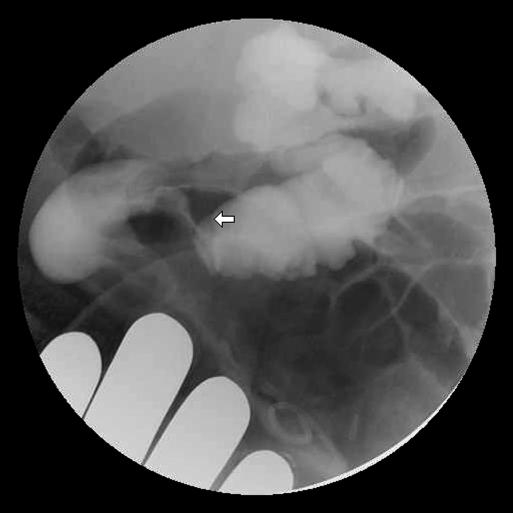

Cecal volvulus is a rare cause of bowel obstruction that carries a high mortality. Recent surgery is known to be a risk factor for the development of cecal volvulus. We present a case of cecal volvulus following laparoscopic nephrectomy and renal transplantation.

盲肠扭转是肠梗阻的一种罕见病因,死亡率很高。近期手术是已知的盲肠扭转发生的一个危险因素。我们报告一例腹腔镜肾切除及肾移植术后发生盲肠扭转的病例。